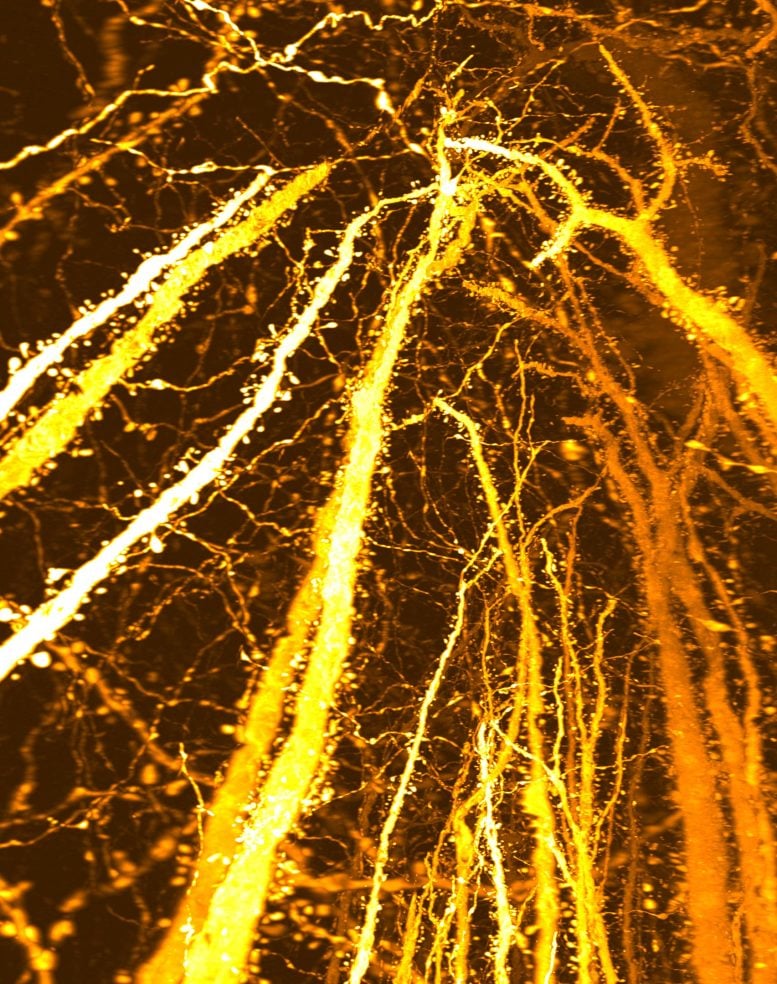

New Synaptic Formation Adolescent BrainThis image shows densely accumulated dendritic spines. Researchers from Kyushu University discovered a previously unrecognized synaptic “hotspot” that forms during adolescence, challenging the long-held view that adolescent brain development is driven mainly by synaptic pruning. Credit: Takeshi Imai / Kyushu University

“We did not set out to study brain disorders,” says Professor Takeshi Imai at Kyushu University’s Faculty of Medical Sciences. “After developing a high-resolution tool for synaptic analysis in 2016, we looked at the mouse cerebral cortex out of curiosity. Beyond seeing the beauty of the neuronal structure, we were surprised to discover a previously unknown high-density hotspot of dendritic spines, the tiny protrusions in dendrites where excitatory synapses are formed.”

Using this method, the team created a complete map of dendritic spines across individual Layer 5 neurons. Their analysis uncovered an unexpected region of extremely high spine density located along the apical dendrite. Further comparisons across developmental stages showed that this dense cluster does not appear early in life but instead emerges specifically during adolescence.

To determine how and when this dense region forms, the researchers followed changes in dendritic spine distribution over time. In mice that were two weeks old and had not yet been weaned, spines were spread fairly evenly along the dendrites. However, between three and eight weeks of age, a period that spans early development through adolescence, spine numbers increased sharply in one specific section of the apical dendrite. Over time, this selective growth led to the formation of a concentrated synaptic hotspot.